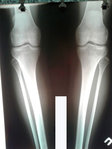

Рентген в 90 дней.

Приезжайте на постепенное распускание аппаратов.

IMG-20181001-WA0057.jpg

IMG-20181001-WA0056.jpg